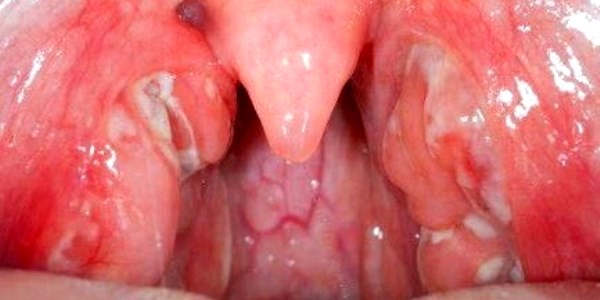

Ниже предоставляется фото больного ангиной горла, как видим, здесь присутствуют множество, противоположных симптомам здорового горла, признаков.

Врачи отмечают, что при ангине горло имеет характерные изменения, которые помогают в диагностике заболевания. В первую очередь, наблюдается покраснение и отек слизистой оболочки глотки. Миндалины, расположенные по обе стороны от горла, могут увеличиваться в размерах и покрываться белыми или желтоватыми налетами, что свидетельствует о наличии гнойного воспаления. В некоторых случаях отмечается наличие язвочек на миндалинах. Также пациенты часто жалуются на боль при глотании, что связано с воспалением тканей. Важно отметить, что при вирусной ангине изменения могут быть менее выраженными, чем при бактериальной. Врачам важно учитывать эти визуальные признаки для правильной диагностики и назначения адекватного лечения.

Фолликулярная. Проявляет себя также как и лакунарная ознобом и высокой температурой, появляется боль, отдающая в ухо, головная и сердечная боль. В горле появляются фолликулы, наполненные бело-желтой жидкостью, размером с зернышко.

Фиброзная. Характеризуется наличием фиброзных бело-желтых налетов на миндалинах, иногда покрывающих сплошной пленкой, что проявляется ознобом и повышением температуры.

Язвенно-пленчатая. Проявляется припухлостями миндалин и образованием язвы на одной из них, возникает ощущение инородного тела в горле и тяжести при глотании, неприятный запах изо рта.

При ангине горло выглядит воспалённым и отёчным. Люди часто описывают его как ярко-красное, с заметными белыми или желтоватыми налётами на миндалинах. Эти налёты могут быть признаком бактериальной инфекции, такой как стрептококк. Пациенты также отмечают, что горло болит при глотании, и это ощущение может сопровождаться сухостью и дискомфортом. В некоторых случаях наблюдается увеличение лимфатических узлов на шее, что свидетельствует о реакции организма на инфекцию. Многие отмечают, что при ангине голос становится хриплым или даже пропадает. Важно помнить, что при таких симптомах стоит обратиться к врачу для диагностики и назначения лечения.